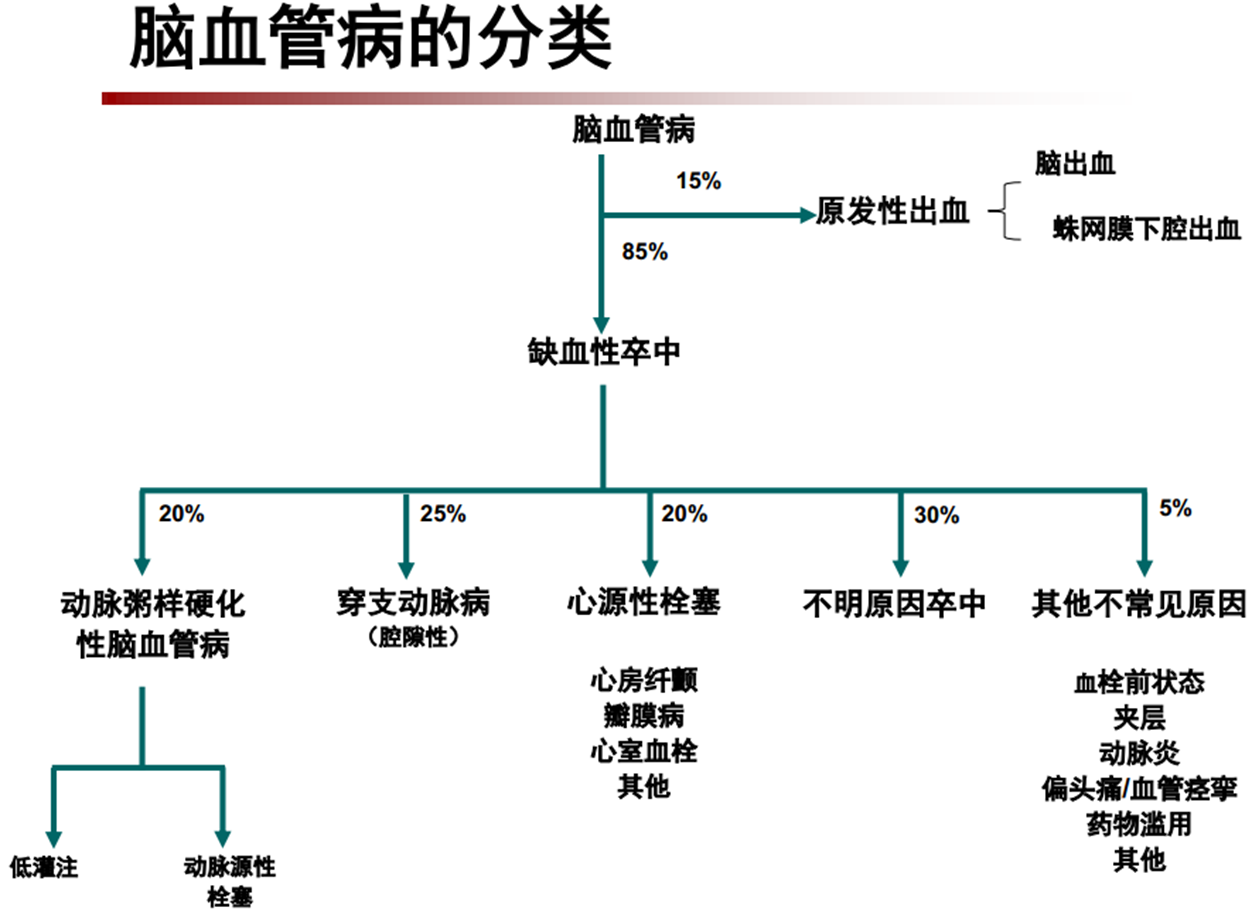

①脑梗死病因分类

②根据不同的病因,使用不同的预防方案

根据病因分型,卒中医生通常会为患者制订个体化的二级预防方案,减低中风再发的风险。